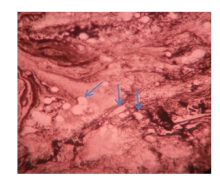

脓肿穿刺液革兰染色病原菌荚膜稍明显、未着色(透明光晕), 内有芽生孢子, 墨汁染色病原菌外层的光晕为厚厚的荚膜, 荚膜包裹着菌细胞, 提示可能是隐球菌(图1~图2)。患者血清隐球菌荚膜多糖抗原滴度为1∶ 1 024。背部及右臀部脓肿穿刺液直接接种血平板, 5 d后培养物由最初的白色逐渐转淡黄或棕黄、湿润粘稠, 状似胶汁(图3)。血液在BacT/ALERT需氧培养瓶中培养5 d后转种血平板, 5 d后生长的菌落形态与脓肿穿刺液一致。脑脊液墨汁染色、隐球菌荚膜多糖抗原及脑脊液培养均阴性。ID32 C和Vitek 2 Compact生化鉴定上述纯培养菌落, 结果为新型隐球菌(Cryptococcus neoformans), 鉴定率=99.9%, 符合率为T=0.84。

| 图2 脓汁墨汁染色(× 1 000) 箭头所指为新型隐球菌。Fig.2 Ink staining of pus (× 1 000) Cryptococcus neoformans is showed by arrows. |